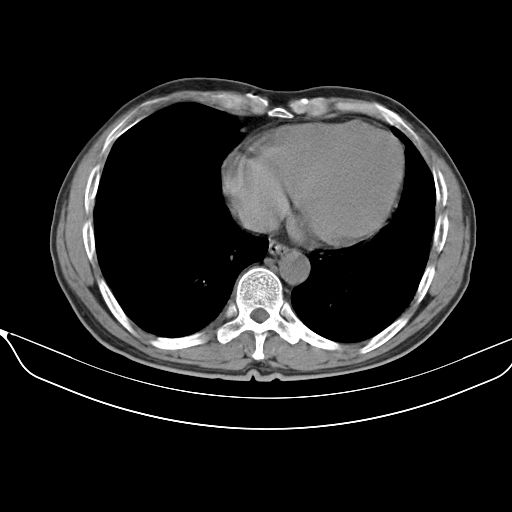

以下是引用shuiyuan在2010-3-1 10:45:00的发言:[br]考虑左肺上叶中心型肺癌伴阻塞型炎症,邻近胸膜受侵。

以下是引用心路寻觅在2010-3-1 10:23:00的发言:[br]1、考虑左肺上叶周围型肺癌[br]2、右上肺陈旧性病灶。[br][br][本贴已被 心路寻觅 于 2010-3-1 10:40:18 修改过]